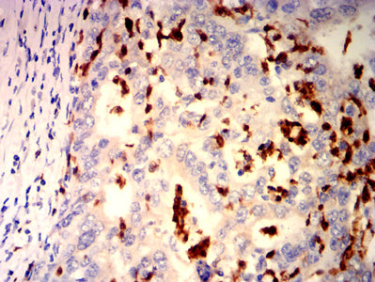

ARG1 Mouse Monoclonal antibody[7D1D]

IHC    1/200-1/1000